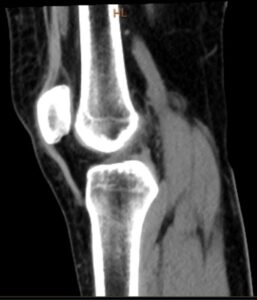

A TAC ao Joelho fornece imagens detalhadas das estruturas ósseas e da articulação femorotibial e patelofemoral, apoiando o diagnóstico de fraturas, desalinhamentos e sequelas pós-traumáticas.

A TAC ao Joelho é uma tomografia computorizada de alta resolução do fémur distal, tíbia proximal e rótula, útil na avaliação de fraturas intra-articulares, consolidação e planeamento cirúrgico.

A TAC ao Joelho é um exame que pode detetar alterações ósseas e articulares, como por exemplo:

- Fraturas e linhas de fratura intra-articulares;

- Desalinhamentos, incongruências e alterações patelofemorais;

- Osteoartrose, osteófitos e geodos;

- Lesões ósseas subcondrais e sequelas pós-traumáticas;

- Tumores ósseos e quistos;

- Sinais de infeção óssea ou articular;